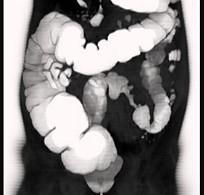

问题 女,56岁,腹胀、腹痛、左下腹包块三月余,无肛门排气,影像检查如图,最可能的诊断是 ( )

选项 A、乙状结肠淋巴瘤 B、乙状结肠息肉 C、乙状结肠结核 D、乙状结肠腺癌 E、乙状结肠crohn病

答案 D